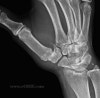

엄지의 X-ray 검사에서 수근중수관절의 관절간격이 협소되고, 연골하 경화, 다양한 정도의 아탈구 또는 탈구 소견이 나타납니다.

X-ray : 엄지 수근중수관절 관절염(1st carpometacarpal joint)